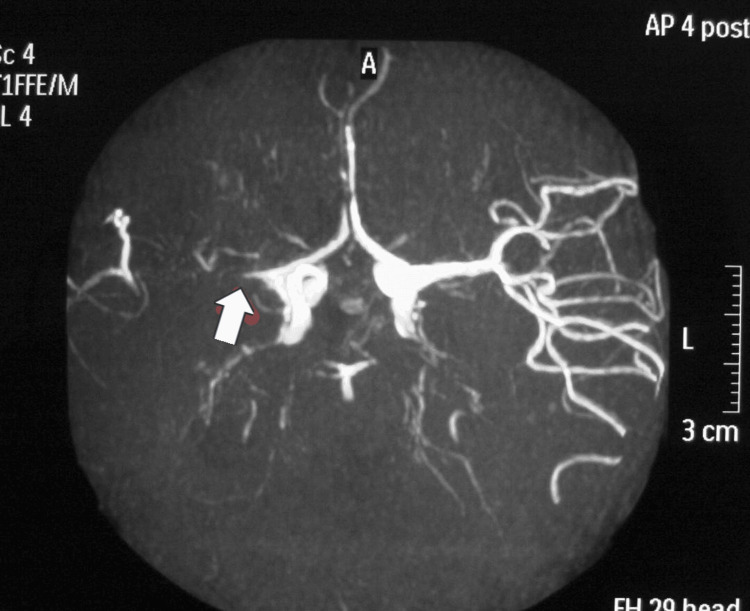

烟雾病(MMD)是一种罕见的脑血管疾病,其特征是双侧颈内动脉和大脑前动脉收缩或阻塞,导致缺血或出血事件。一位28岁的白人女性,有双侧烟雾病史,在怀孕38周时接受剖宫产。手术前后的处理包括停用阿司匹林,密切监测血流动力学,并给予全身麻醉。一个健康的男婴通过剖宫产分娩,母亲和婴儿在第三天出院,没有任何并发症。该病例是希腊首次记录的妊娠期烟雾病病例。通过早期识别、量身定制的分娩计划以及产科、神经病学和麻醉团队之间的协作护理,有可能取得成功的结果。需要更多的多中心研究来为这一高危患者群体制定标准的管理方案。

Moyamoya disease (MMD) is a rare cerebrovascular disorder characterized by the constriction or obstruction of the internal carotid and anterior cerebral arteries bilaterally, leading to either ischemic or hemorrhagic events. A 28-year-old Caucasian female with a history of bilateral MMD was admitted for a scheduled cesarean delivery at 38 weeks of pregnancy. The management around the surgery involved stopping aspirin, closely monitoring hemodynamics, and administering general anesthesia. A healthy male baby was delivered via cesarean section, and both the mother and infant were discharged on the third day without any complications. This case represents the first recorded instance of MMD during pregnancy in Greece. Achieving successful results is possible through early identification, tailored delivery planning, and collaborative care among obstetrics, neurology, and anesthesia teams. Additional multicenter research is necessary to create standard management protocols for this high-risk patient group.